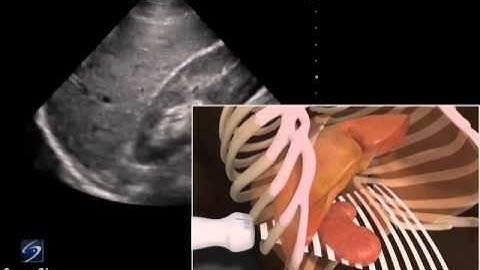

How To: EFAST - Subxiphoid View 3D Video